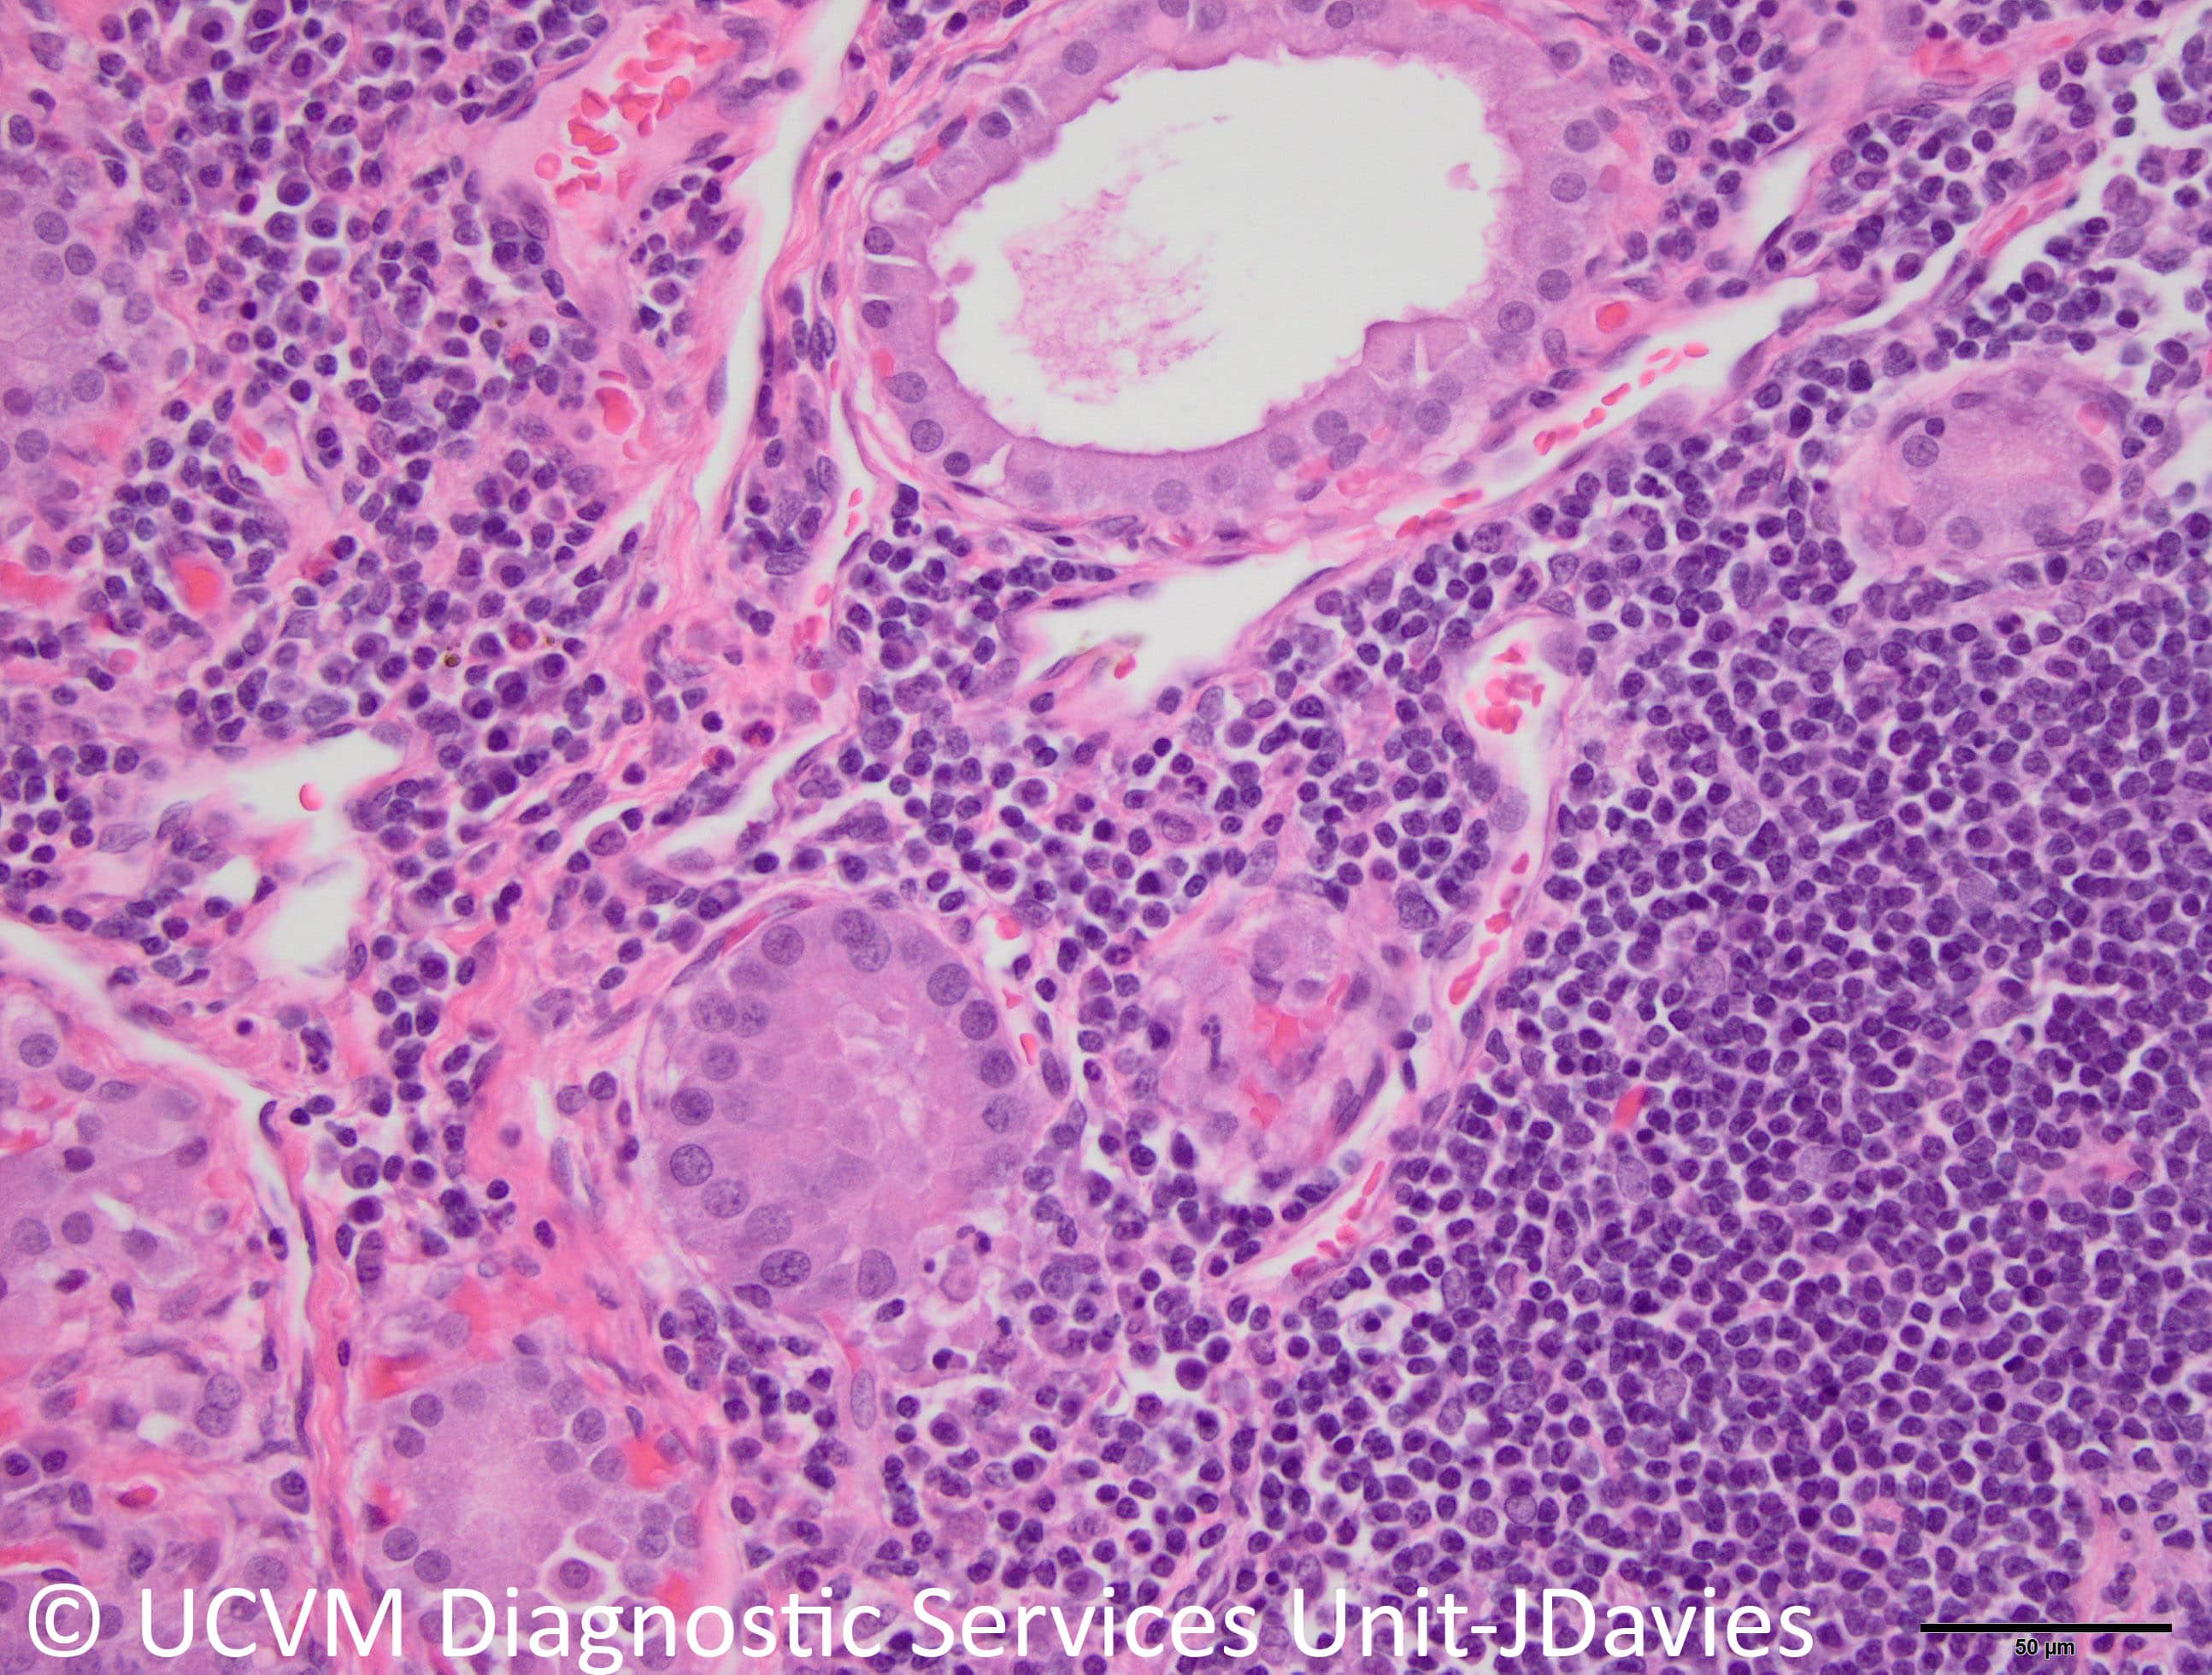

Specimen: Thyroid gland

Shown: Lymphocytic thyroiditis in a dog with hypothyroidism